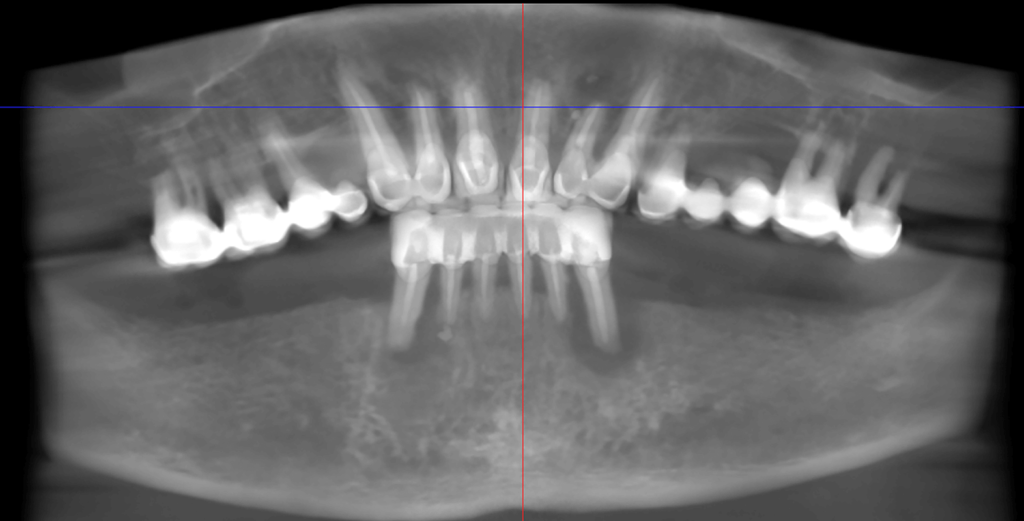

Пациенту сделали КТ-снимок и пригласили в кабинет врача. При осмотре были обнаружены металлокерамические мостовидные протезы справа и слева на верхней челюсти, а также на переднем участке нижней челюсти. Съемный протез на нижней челюсти, покрывавший участок жевательных зубов. Протез слева был подвижен вследствие подвижности опорных зубов первой степени на которых был зафиксирован.

На КТ-снимках врач обнаружил:

- генерализованный пародонтит

- мостовидный протез на зубах 1.7, 1.6, 1.5 и 1.4 с опорой на 1.7, 1.6 и 1.5 зубы

- на зубах 1.1, 2.1 единичные коронки

- на зубах 2.2, 2.3. и на 1.3, 1.2 две коронки

- на зубах 2.4, 2.5, 2.6 и 2.7 мостовидный протез с опорами на 2.4, 2.6 и 2.7 зубов.